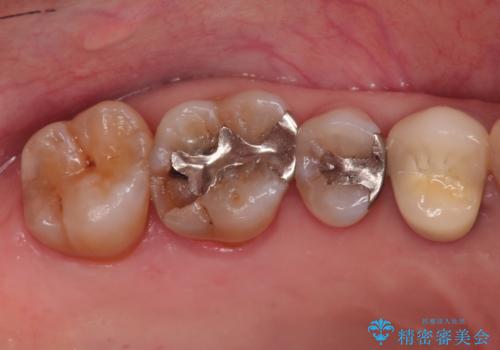

- 他院で入れたセラミックインレーがかけたことを主訴に来院されました。

他の部位にもむし歯を認めたため、優先度の高い歯から治療を行っております。

咬合力が強くかかる部分には欠けるリスクのほとんどない金属を用いることが最良ですが審美性に劣ります。

今回は白い材料での修復を希望されたため、欠けるリスクが高いセラミックインレーは避け、セラミッククラウンにて治療を行いました。